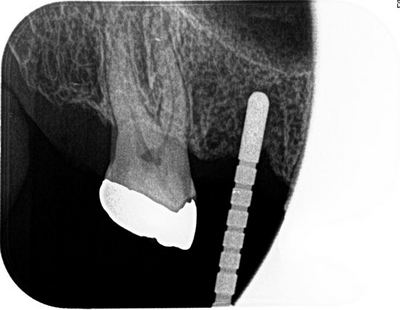

かなりコーンカットのレントゲンですが、1目盛り2mmですので

上顎洞底まで約3mm程度であることがわかります。